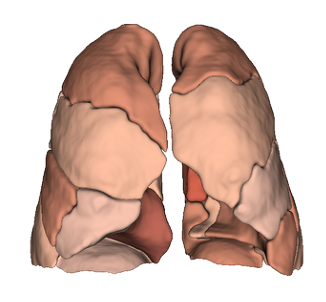

- Segmentation of anatomical structures up to sub-segmental level

- Quantitative analysis of complex lung patterns and diseased regions

The modular capabilities can be integrated into early-stage R&D projects and further developed toward regulatory and clinical readiness. LungQ® software modules can be then embedded into interventional systems and clinical workflows to support, advancing personalized procedural planning and intra-operative guidance for high-precision lung interventions, as well as enabling longitudinal post-procedural assessment.